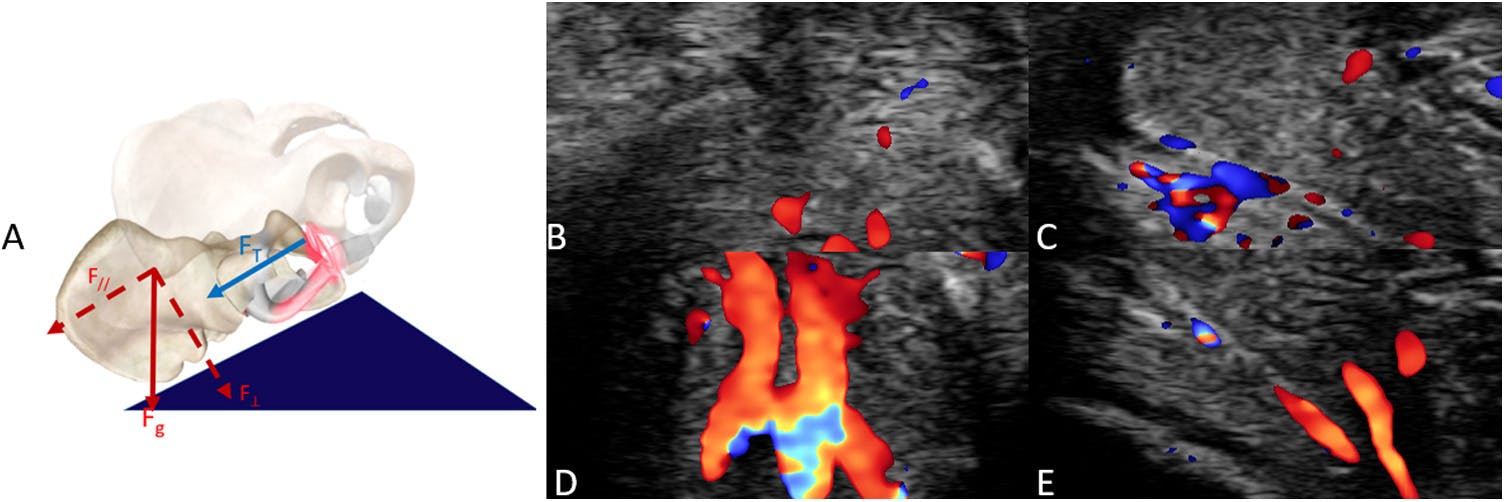

Ved at undersøge et par med ultralyd, mens de havde sex i ti minutter i fem forskellige stillinger, kan Lovie og og en kollega konstatere, at missionæren med giver mest blodcirkulation i klitoris, hvilket i princippet øger chancerne for orgasme.

Og her taler vi ikke kun om den synlige del af klitoris, altså klitorishovedet, men hele det klitorale kompleks med ben og svulmelegemer:

Og ikke nok med det, Kimberly fandt også ud af, at brug en såkaldt sexpude, som hæver kvindens underliv i missionæren, hvor hun ligger nederst, booster stillingen samt giver dybere penetration.

Vi har før skrevet om sexpude som simpelt og effektiv sexhack. En sexpude har form som en kile.